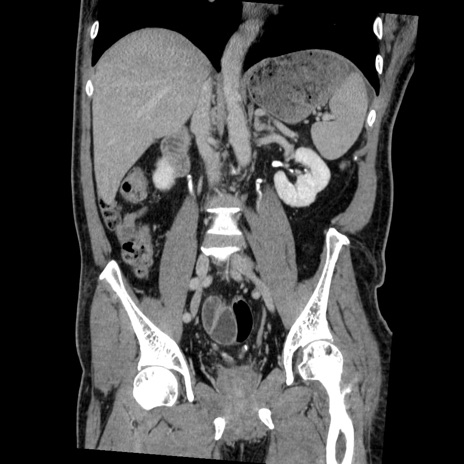

症例22(冠状断像)

【症例】50歳代男性

【主訴】腹痛

【現病歴】AVMからの被殻出血のため回復期リハ病棟入院中。 本日午後3時頃急に下腹部痛が出現した。

【既往歴】AVM、被殻出血、虫垂炎、高血圧

【身体所見】意識晴明、左半身不全麻痺、会話の理解は良好、36.5°C、腹部:膨隆、全体に板状硬、下腹部正中に圧痛点あり、反跳痛-、筋性防御不明、右下腹部にope scar

【データ】WBC 9400、CRP 0.06